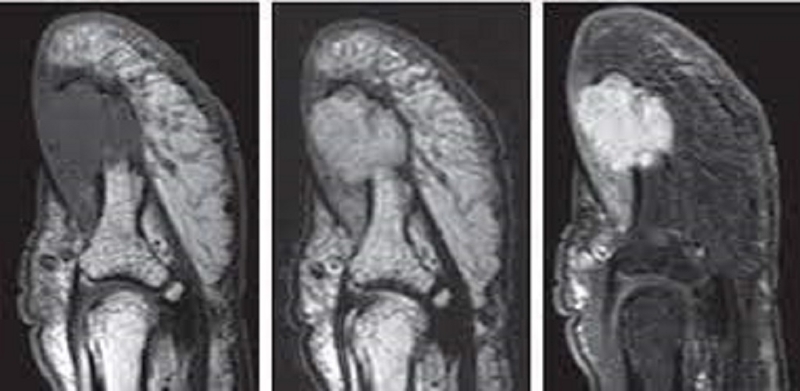

• Cộng hưởng từ (MRI): Giúp đánh giá được chính xác khối u nhưng lại có giá thành khá cao. Trong một vài trường hợp khối u đồng tín hiệu với khối u của bệnh nhân thì khó có thể phát hiện ra.

https://nhathuoclongchau.com.vn/auth/post/edit/66296 2 Hình ảnh MRI của u cuộn mạch ngón cái

Đặc biệt, siêu âm Doppler thường được áp dụng trong chẩn đoán phân biệt u cuộn mạch và các loại u khác của móng tay. Phim MRI cùng giác bác sĩ điều trị trong lựa chọn đường mổ thích hợp để loại bỏ khối u.